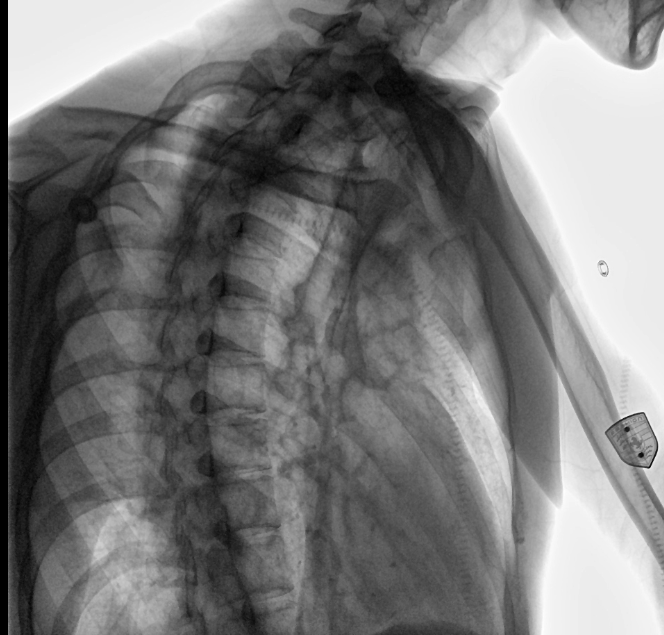

位于衡水市中醫(yī)醫(yī)院的動態(tài)平板數(shù)字化X射線系統(tǒng)DTP571具備高速高清點片功能。這是一款對放射科十分友好的產(chǎn)品。因為它把高速和高清點片結(jié)合,既能方便影像技師有效地抓拍需要的病灶的影像,又能給予影像醫(yī)生清晰的影像進行診斷。